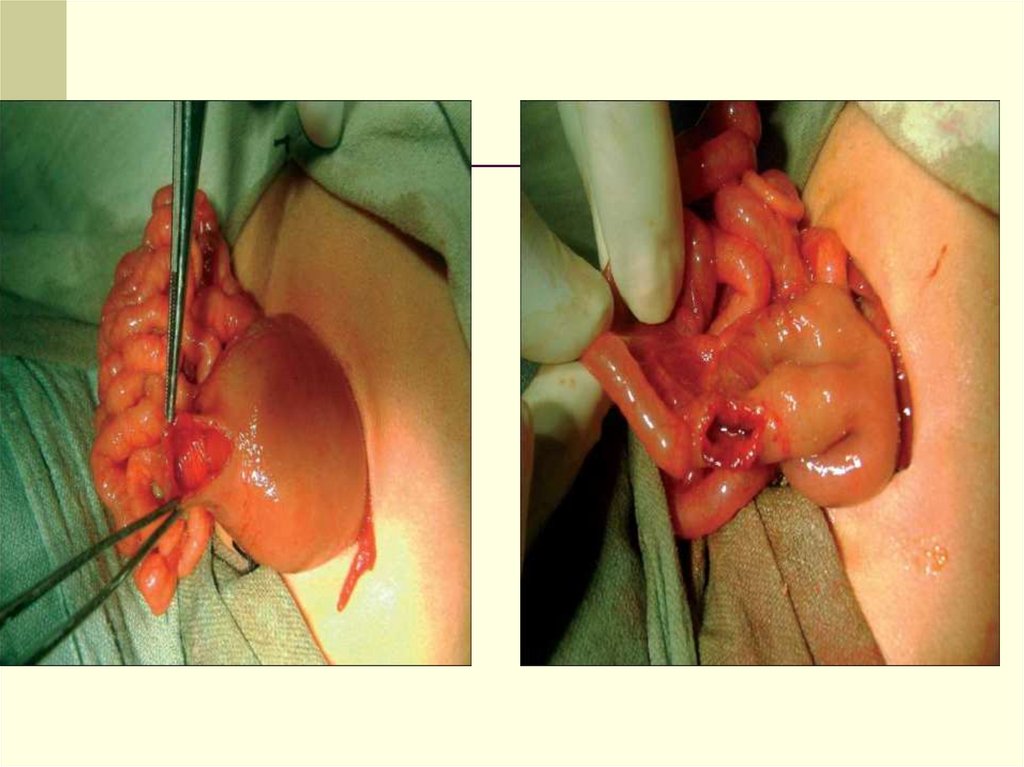

28. Показания к хирургическому лечению

Неэффективность консервативного лечения

Этапы:

1) Поперечная супраумбиликальная лапаротомия

2) Энтеротомия с эвакуацией мекония

3) Промывание тонкой кишки 1% раствором Nацетилцистеина

4) Ушивание энтеромического отверстия при

нормальном состоянии кишечника

5) Энтеростомия

29. Варианты хирургического лечения

Энтеротомия с промыванием кишки

теплыи изотоническим раствором

Сцеживание мекония дистальнов толстую

кишку или энтеротомия.

Энтеростомия по Бишоп – Кооп

Ретроградное дренирование толстой

кишки с промыванием просвета

Энтеростомия по Микулич

Проксимальная энтеростомия по Сантулли

31. Bishop-Koop энтеростомия (оптимальный способ)

Позволяет уменьшить интраоперационную травму

кишечника в неонатальном периоде.

Позволяет восстановить проходимость кишечника

без отведения кишечного содержимого по стоме

Обеспечивает возможность проведения катетера

дистально в толстый кишечник для ретроградного

промывания ободочной кишки

Позволяет без обширной лапаротомии закрыть

энтеростому методом лигирования